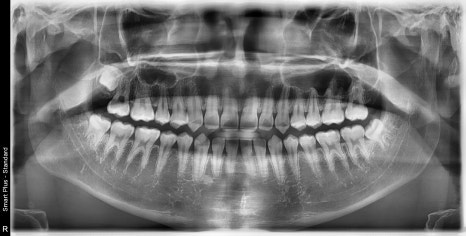

| 발치 전 | 발치 후 |